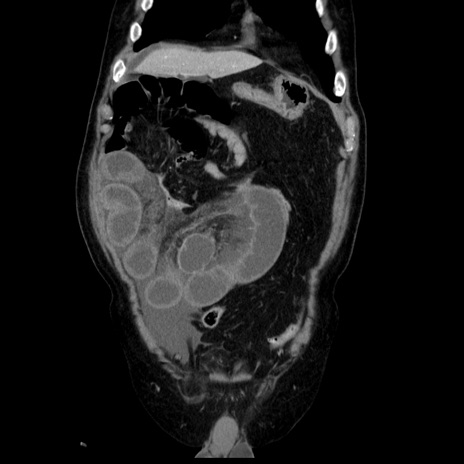

症例30(冠状断像)

【症例】80歳代男性

【主訴】臍周囲痛

【現病歴】約6時間前から臍下部痛が出現。次第に腹部膨隆・背部痛も生じてきたため来院。背部痛の場所は変化しない。

【既往歴】腎盂腎炎

【身体所見】意識清明、BT 36.3℃、BP  131/87mmHg、P 87bpm、SpO2 100%(RA)、臍周囲自発痛・圧痛あり、反跳痛なし、自発痛部位に一致して板状硬あり、腹部膨隆、腸雑音減弱、CVA tenderness両側陰性。

【データ】WBC 19600、CRP 0.33

横断像